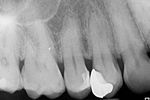

Revisionsbehandlung eines Unterkiefermolaren (37) vor geplanter Überkronung (Dr. Maik Göbbels) Download